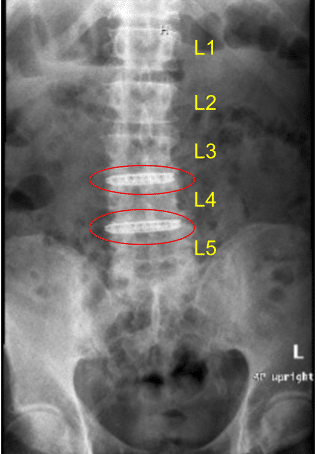

Case Study: Anterolateral lumbar discectomy and arthrodesis via left flank retroperitoneal approach

A patient with a past medical history of coronary artery disease and severe end-stage renal disease on three times weekly dialysis with intractable back pain, who failed nonoperative management.

MRI and CT of his lumbar spine demonstrated severe degenerative disc space breakdown at L3-L4 and L4-L5 and accordingly they were offered a surgery for discogenic pain. The risks and potential benefits of surgery were extensively explained to the patient.

Disc space narrowing at L3-L4 and L4-L5

They signed informed consent and were brought to the operating room for the aforementioned procedure. The findings of the preoperative lumbar spine x-ray are shown above and the patients also had a preoperative computerized tomography scan (CT scan) shown above.